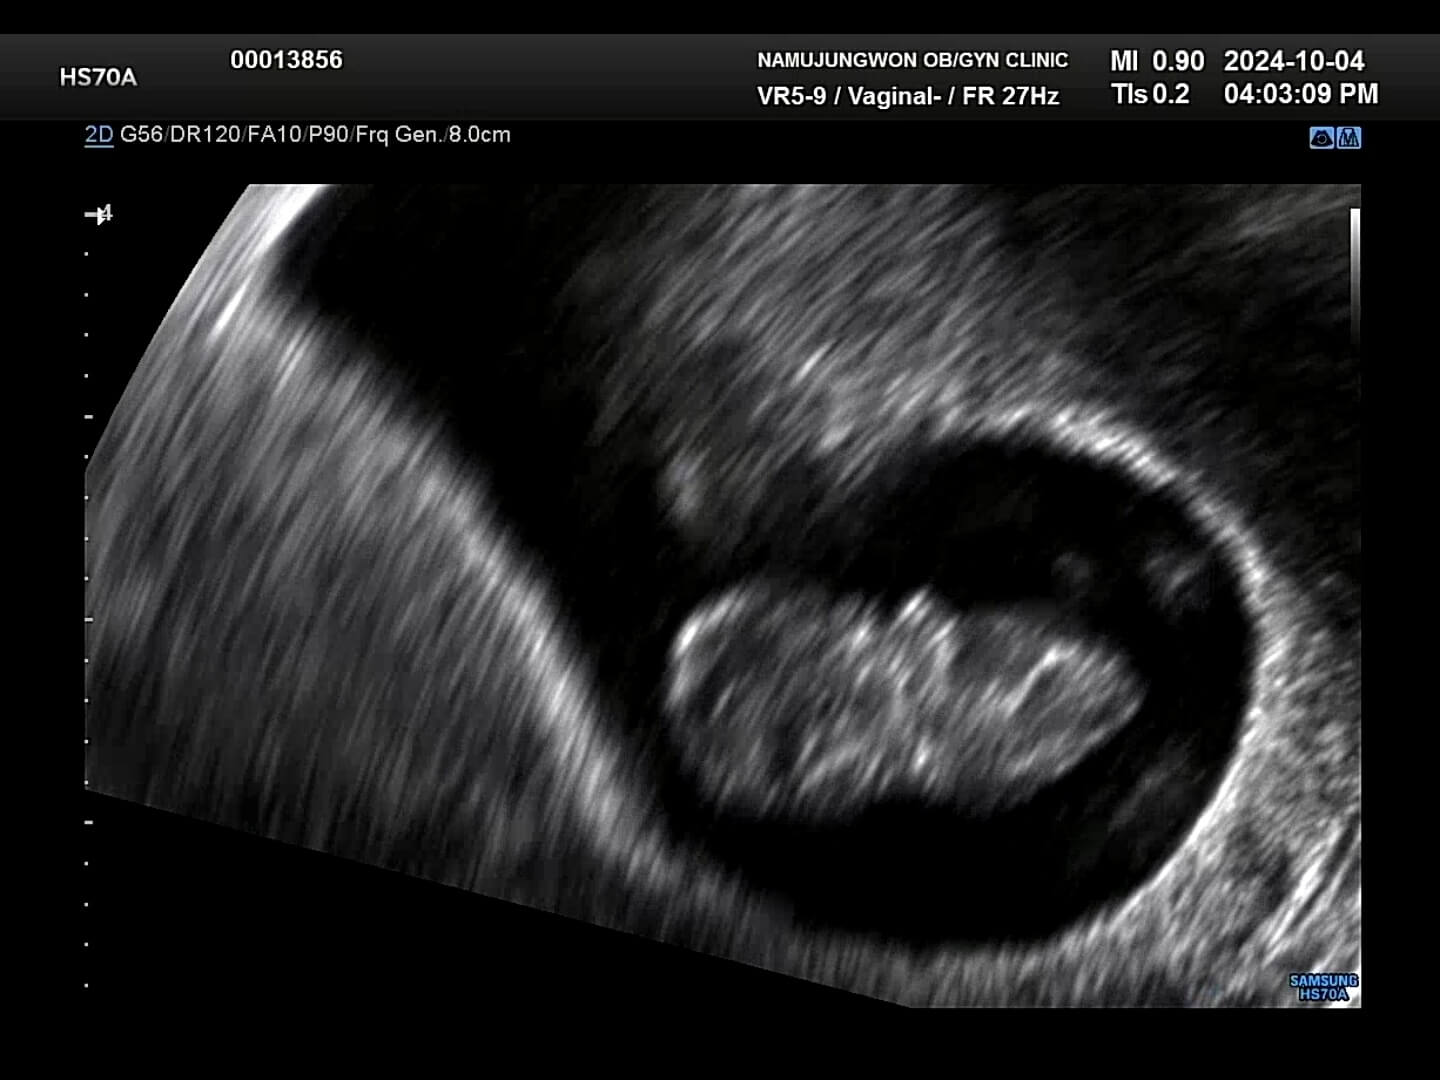

12주-입체초음파 12주에는 첫 입체초음파를 보게 되면서 팔, 다리가 잘 형성되었는지 정도를 보는 것 같아요. 12주부터 '태아'라고 부르기도 한답니다. 우리 꾸미는 처음에는 등을 돌리고 있다가 서서히 얼굴을 보여줬습니다. 벌써부터 귀여워요! 아들인지 딸인지 너무 궁금했는데요, 성별은 입체 초음파가 아닌 일반 초음파로 봐야한다고 하셨어요.